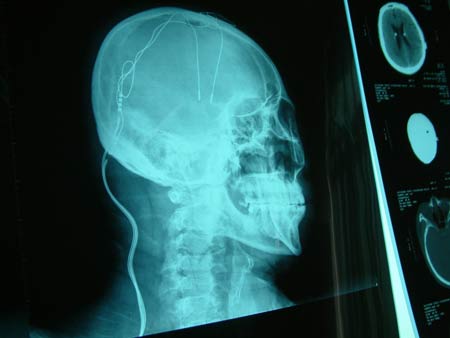

手術后,醫生為高春新固定頭部。

從片子上看,腦內電極清晰可見。

2月4日,吉林大學第一醫院神經外科經過6個小時的緊張手術,對高春新實施了雙側丘腦底核刺激器植入術。醫生運用高科技手段,在高春新的腦袋里植入了兩個電極,然后將2條導線通過皮下延伸到其右胸部,與安放在這里的刺激器相連接。

據吉大一院副教授邱吉慶介紹,兩個電極被安放在了高春新的雙側丘腦底部,電極產生的電流可以控制并調節腦內不正常的細胞活動訊息,進而有效地改善其身體的活動能力。